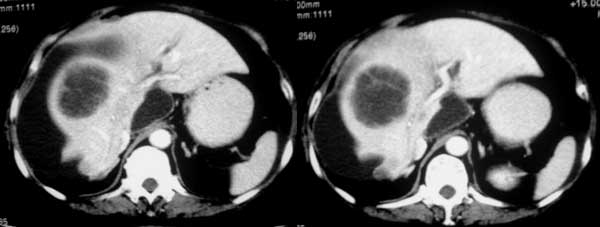

女,70岁,腹痛一月。

05年5月19日平扫片

增强片 动脉期

门脉期

延迟期

好病例!05年8月17日ct片见肝右缘巨大新月状囊性水样密度灶,肝裸区及右侧肝肾隐窝见囊性水样密度灶,相应肝实质受压变形,增强后病灶内及无包膜强化,胆囊窝内未见胆囊,在胆囊窝右侧肝实质内见囊性水样密度灶(考虑肝内胆囊),胆囊肿大,增强后,其内见不均匀轻度强化影,厚壁强化胆囊周围肝实质低密度强化影.05年5月19日比较有明显好转,但胆囊还肿大,壁还厚,胆总管轻度扩张.

诊断:1急性肝内坏死性胆囊炎并肝脓肿.

2肝右缘巨大新月状囊性水样密度灶:定位是膈下还是肝包膜下.定性是脓肿还是胆汁漏形成假囊肿.

两次片比较(间隔三个月)胆囊窝肝内低密度灶增大,内部有分隔,周围有环形强化,肝内出现囊样低密度影,边界清,肝门部有囊样低密度影,肝左叶胆管扩张,胆总管稍扩张,胆囊体积大,壁不均匀增厚。

考虑:1。慢性胆囊炎并穿孔,肝脓肿形成。2 肝囊肿。3胆总管扩张原因?[emb18]